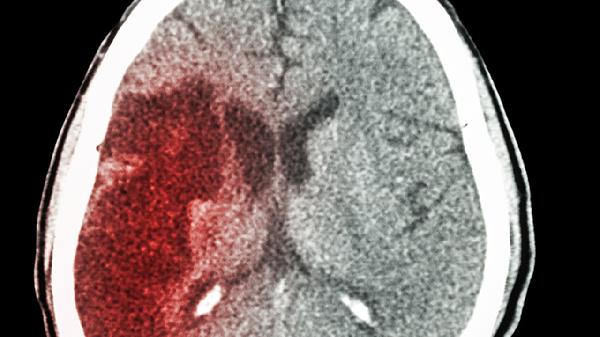

50岁后血管危.机潜伏!这5种食物再馋也要少吃,当心脑梗找上门

血管就像城市里的输水管道,用久了难免会积攒"水垢"。特别是年过五十之后,那些年轻时欠下的"血管债"开始悄悄算总账。别以为头晕手麻只是小毛病,说不定就是血管在拉警.报!今天要说的这几种食物,堪称血管"隐形杀手",快看看你家餐桌上有没有?